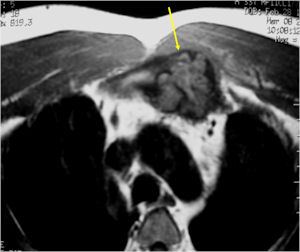

- There may be expansion of bone, cortical thinning and cortical breakthrough. A soft tissue mass may accompany this lesion but the soft tissue component is usually contained by the periosteum.

- The periosteum remains intact around the soft tissue component. Might need a CT scan to detect the subtle calcification (Egg Shell Rim of Calcification) associated with an intact periosteal reaction

CT Scan:

- More useful for detecting mineralization and evaluating extent of bone destruction than plain X-ray

MRI:

- Also useful in determining extent

- There is often extensive edema around the tumor in the surrounding bone and soft tissues that can lead to a misdiagnosis of a malignant tumor.